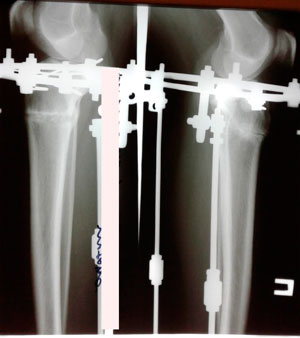

Дата операции - 12.07.2019г.

Дата снятия аппаратов - 17.10.2019г.

Срок сращения - 95 дней.